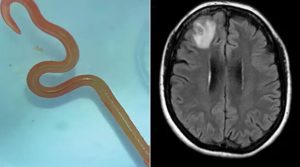

Soffriva di depressione e vuoti di memoria, una donna di 64 anni, australiana, si è recata da un neurochirurgo per...